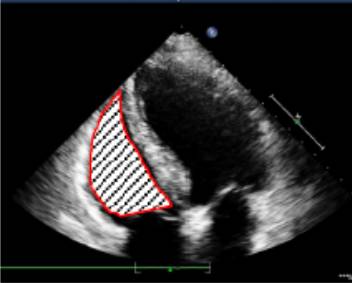

2、左心室容积的测量

双平面法(改良Simpson法):分别于收缩末期和舒张末期,在心尖四腔心及两腔心切面手动描记心内膜以计算容量。描记过程中,应将乳头肌从室腔中删除。心尖四腔切面上左心室面积的基底部边界应由二尖瓣环侧缘与间隔缘之间的直线来确定,而在两腔切面,则用瓣环前缘与下缘之间的直线来确定。

双平面法示意图